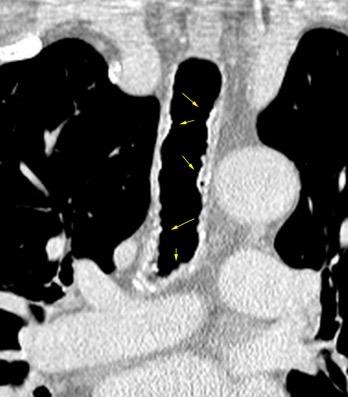

Traqueobroncomegalia de Mounier-Kuhn

Dilatación marcada de tráquea y grandes bronquios.

Traqueobroncomalacia 67% + Protrusión del tejido músculo-membranoso redundante entre los anillos cartilaginosos.(diverticulosis traqueal)

Infección respiratoria recurrente (88%)

Debilidad del aparato muco -ciliar Fumadores.

Schmitt P et al. Respiratory Conditions Associated with Tracheobronchomegaly (Mounier-Kuhn Syndrome): A Study of Seventeen Cases. Respiration 2016

Wegner F. CT of Mounier-Kuhn Disease. Radiology 2020